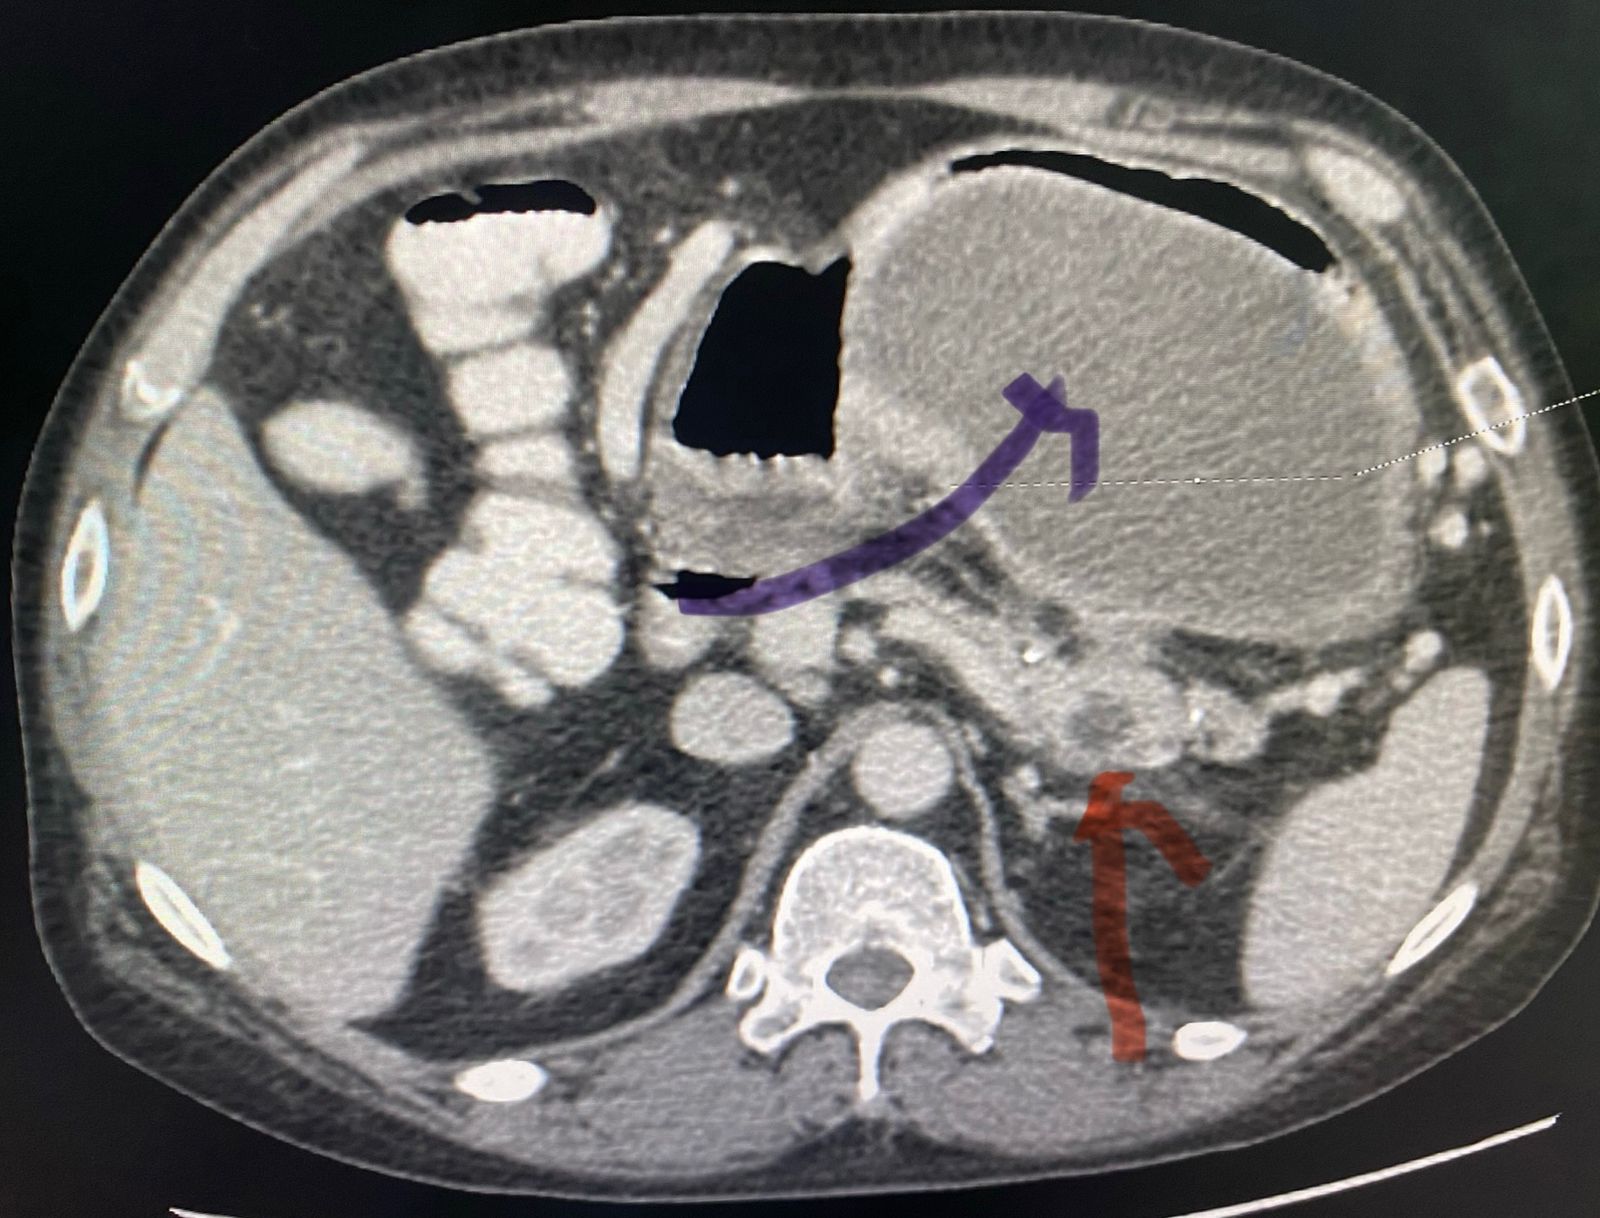

A 54 year old gentleman presented with acute abdominal pain since 5 days accompanied by vomiting. His investigations revealed a suspicious pseudo cyst of pancreas on ultrasonography and CT scan of the abdomen. A careful re look of the CT scan followed by an MRCP suggested a leak from pancreatic duct at the junction of body and tail of the pancreas. This had led to formation of a pseudo cyst (image - pseudo cyst : blue arrow, duct leak area - red arrow).